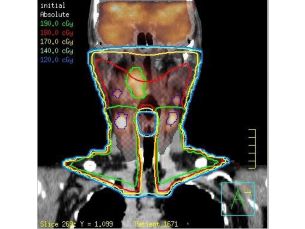

Planificación de tratamiento Pinnacle3

Las herramientas de planificación de tratamiento rápidas, precisas e interactivas han convertido a Pinnacle³ en un líder en planificación de tratamiento de radiación. Con una reputación de rendimiento, fiabilidad y un entorno de planificación flexible e intuitivo que simplifica el flujo de trabajo, Pinnacle³ se ha convertido en el producto de elección de muchos centros oncológicos líderes a nivel mundial.